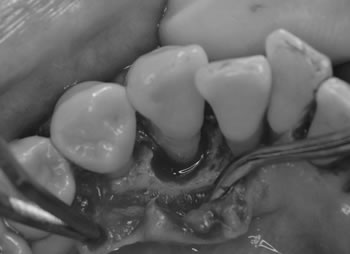

■術中

歯の周りには骨が破壊され、感染源も残っていました。

歯周病治療にのみ、厚労省が認可している骨移植剤 バイオスを患者さんの同意のもと使用しました。